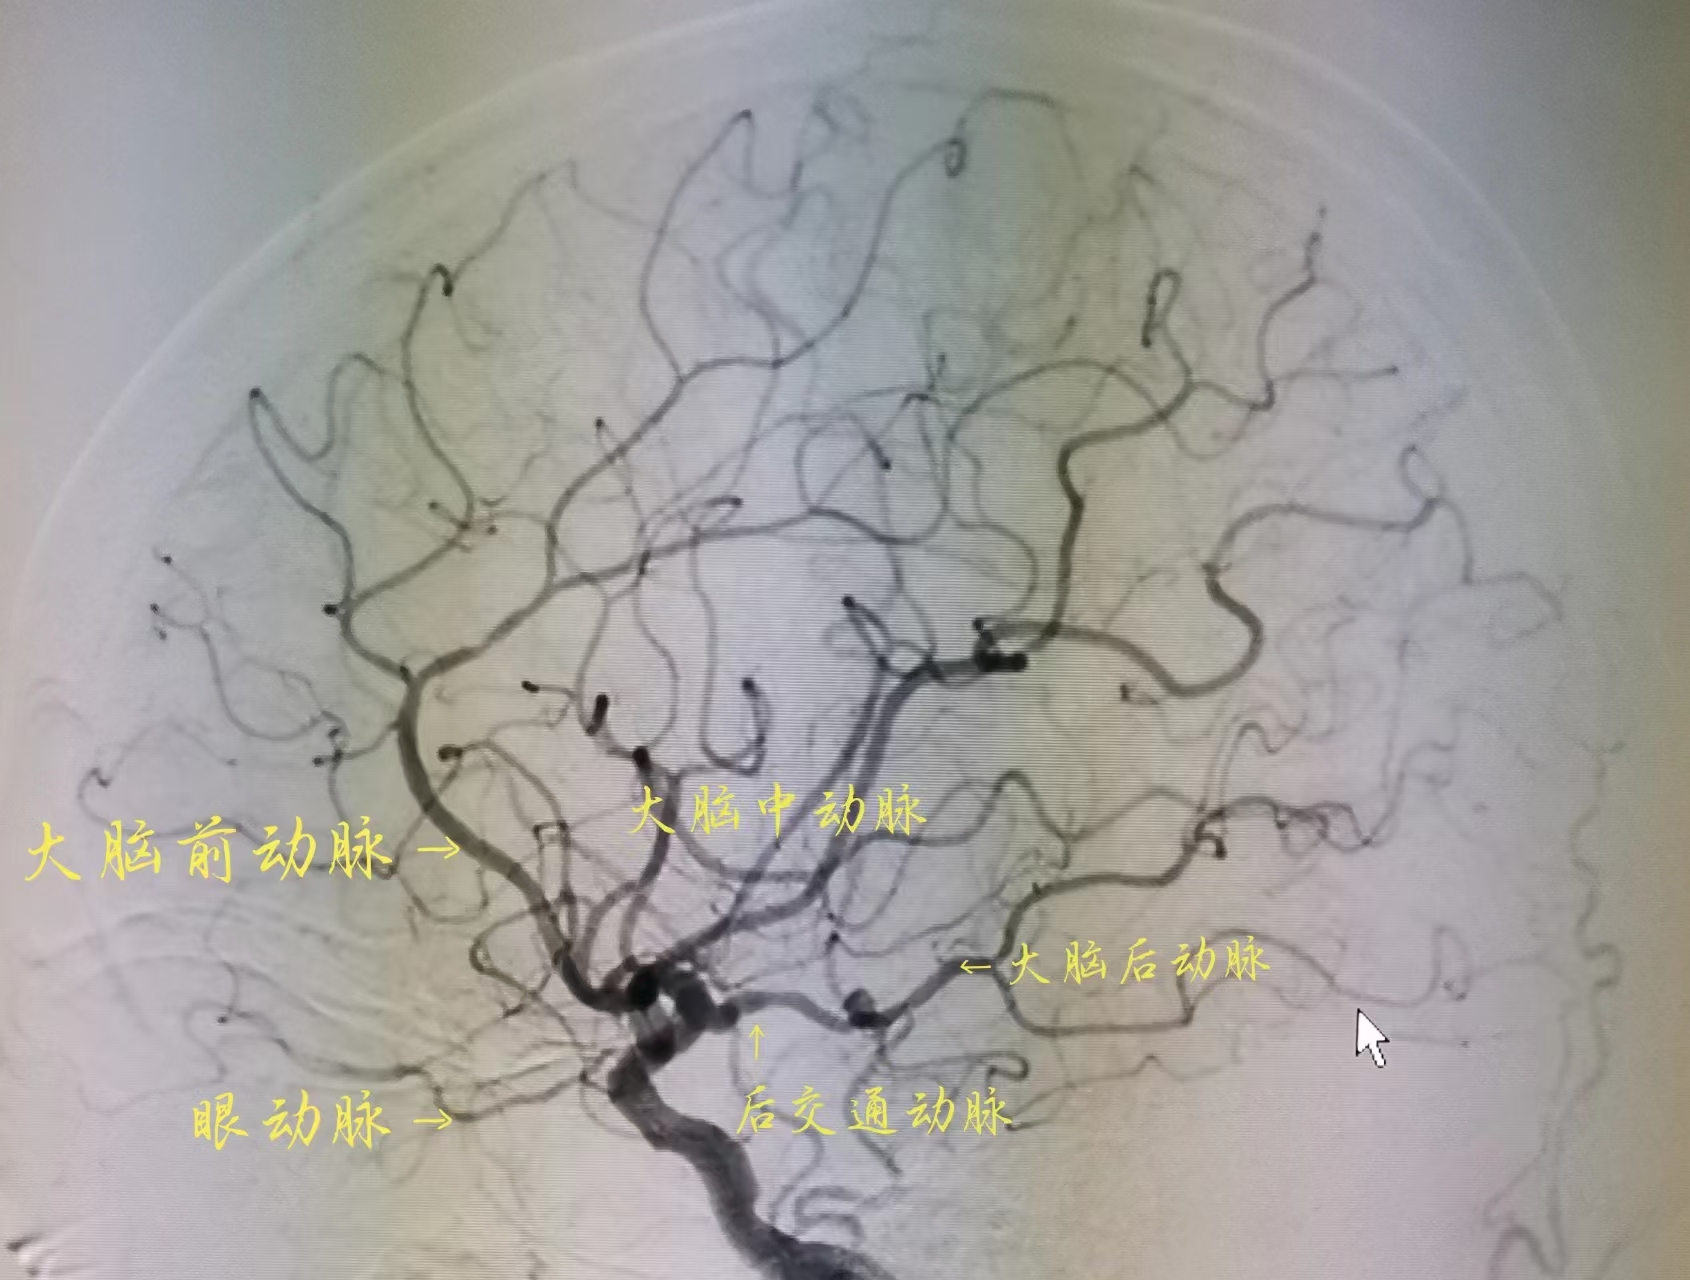

脑交通动脉并非单一血管,而是构成大脑动脉环(Willis环)的核心成员,主要包括前交通动脉和后交通动脉。前交通动脉连接左右大脑前动脉,负责协调大脑半球前部的血流;后交通动脉则搭建起颈内动脉系统与大脑后动脉系统的“桥梁”,让前、后脑部的血液可以互通有无。正常情况下,这些交通动脉的血流平稳且低调,不会干扰各主干血管的常规供血。

当脑血管主干因血栓、动脉粥样硬化等原因发生闭塞时,缺血区域的血压会随之下降,健康血管与闭塞血管之间形成的压力差,会迅速激活脑交通动脉的代偿功能。此时,血液会顺着交通动脉的“通道”,从供血正常的区域流向缺血区域,为濒临坏死的脑细胞输送氧气和营养,尽可能缩小缺血范围,减轻脑卒中的损伤程度。交通动脉相当于为脑血管健康增加了一道“保险”,能更好地抵御缺血性脑血管疾病的侵袭。